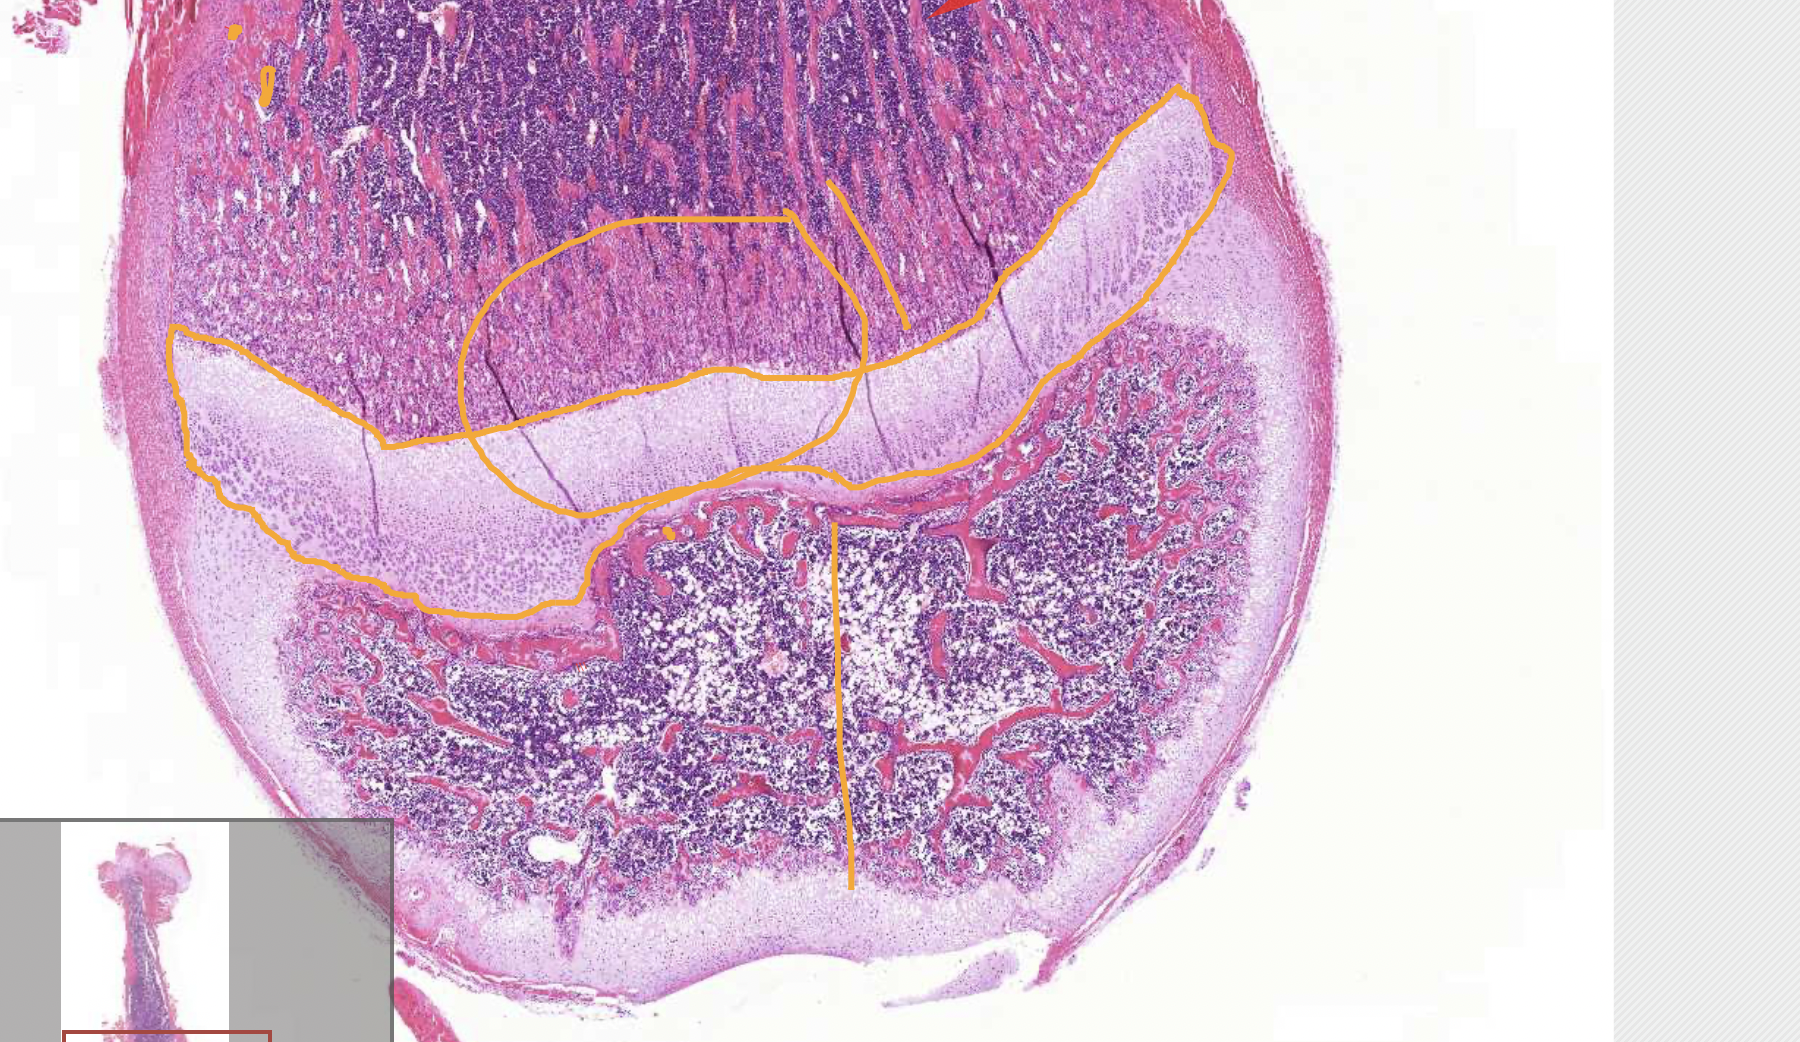

term image

• primary region of ossification (deeper in the bone)

• secondary region of ossification (outer) - helps to not disturb the joint with growth

• cortical/compact bone - dense, important for bone strength

• trabecular bone - harbour precursor bone cells, haemopoietic cells (red marrow) and fat cells (yellow marow)

• growth plate - longitudinal growth (cartilage then bone)